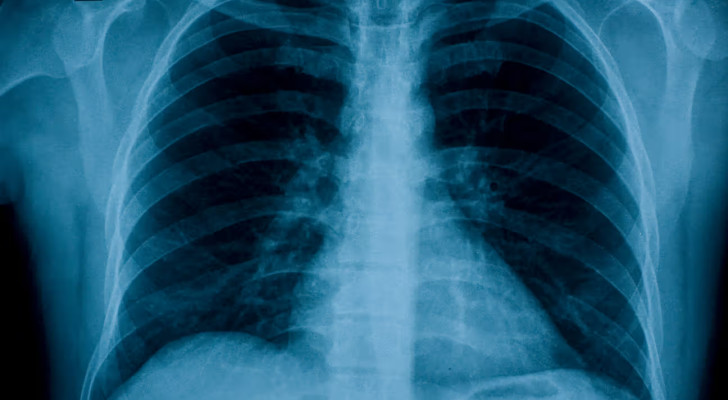

في تقرير نشر في مجلة "ميد"، شرح الجراحون بالتفصيل كيف استأصلوا رئتي رجل مصابتين بعدوى شديدة، وزرعوا له بعدها رئة مزدوجة...

وتفصيليا، أصيب الرجل بمتلازمة الضائقة التنفسية الحادة (ARDS)، بعد أن بدأت حالته بالإنفلونزا وتطورت بسرعة إلى التهاب رئوي بكتيري أدى إلى فشل رئوي، قلبي، وكلوي. ومع تدهور حالته، أصبح زرع الرئتين الخيار الوحيد لإنقاذ حياته، إلا أن جسده لم يكن مستقرا بما يكفي لإجراء العملية فورا.

في خطوة غير مسبوقة، طور الفريق الطبي نظام "رئة اصطناعية" يحل مؤقتا محل الرئتين. ويعمل هذا النظام على أكسجة الدم وإزالة ثاني أكسيد الكربون ودعم الدورة الدموية، ما يسمح للأعضاء الحيوية بمواصلة العمل حتى في غياب الرئتين.

وبعد استئصال الرئتين المتضررتين، بدأت حالة المريض تتحسن، واستقر ضغط دمه، وتم السيطرة على العدوى. وبعد يومين فقط، توفرت رئتان من متبرع، وأجرى الجراحون عملية زرع رئة مزدوجة بنجاح. واليوم، يعيش المريض حياة طبيعية مع وظائف رئوية سليمة بعد أكثر من عامين على العملية.